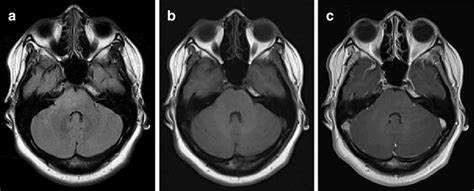

术后早期放疗对高级别胶质瘤重要,一般认为手术与放疗的等待时间在6 周以内是可以接受的。放疗的标准基于CT和MRI的影像学表现以及肿瘤的组织学特征。放射治疗肿瘤学组和欧洲癌症治疗组织关于高级别胶质瘤放疗的建议是以局部照射为主,靶区应参考术前MRI范围和术后脑组织移位情况。高级别胶质瘤周围常常有水肿区,实际放疗时会根据肿瘤生长走行、病理类型等进行靶区外扩,不过中线的胶质瘤一般不进行对侧的照射。